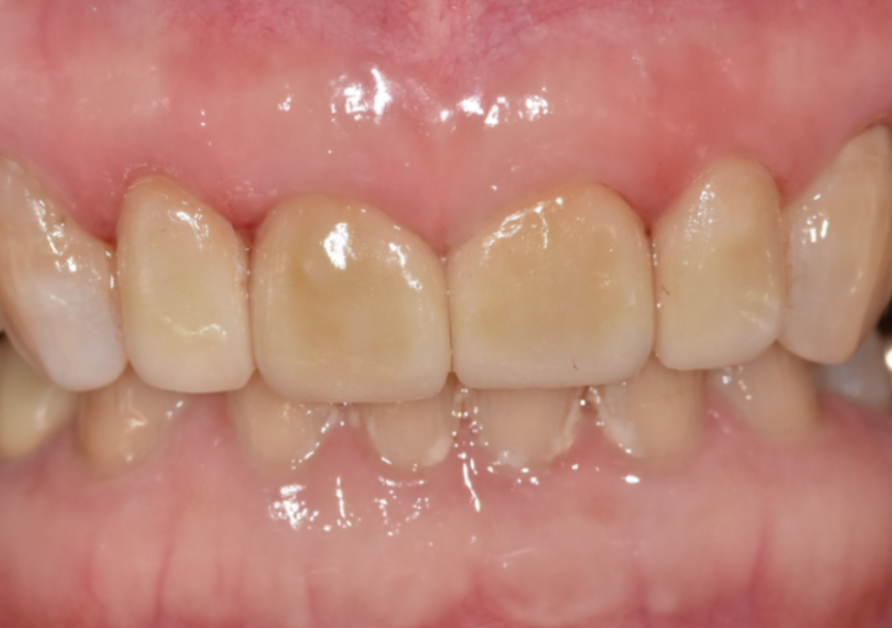

이 환자분은 70대 여성입니다.

젊을 때부터 앞니 사이가 벌어져 있었고

그 틈을 레진으로 메워 사용해 오셨다고 해요.

처음에는 괜찮았지만 나이가 들며

레진이 깨지고 떨어지는 일이 반복되자

“이번에는 제대로 고쳐보고 싶다”며 내원하셨습니다.

입안을 자세히 보니

앞니 사이를 메운 레진이 깨져 있었고,

그 양옆 작은 앞니가

다른 치아보다 눈에 띄게 작았습니다.

이렇게 주변 치아보다 유난히 작은 치아를

‘왜소치’라고 부릅니다.